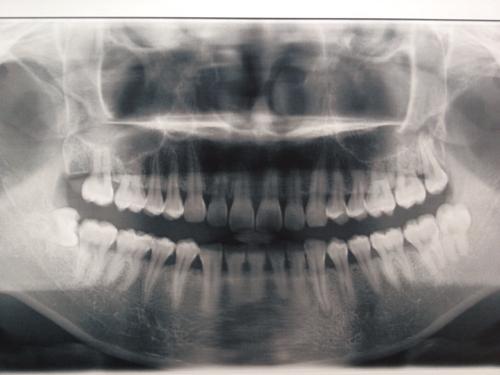

牙齿x光片,会看的大神请进.

正常牙齿全景片